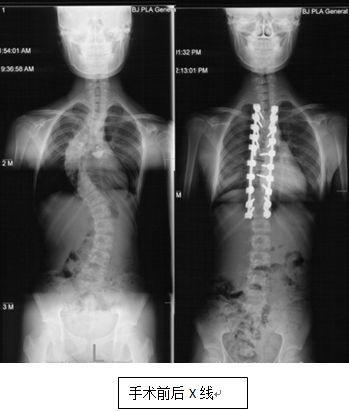

脊柱侧弯,顾名思义,就是脊柱在X光片上呈现侧弯的形态。这种疾病在成年人中并不少见,据统计,我国成年人脊柱侧弯的发病率约为2%-3%。脊柱侧弯不仅会影响外观,还会导致腰背疼痛、活动受限等问题。

脊柱侧弯成人正骨的效果因人而异。一般来说,坚持练习正骨视频中的动作,可以缓解腰背疼痛、改善活动受限等问题。对于严重的脊柱侧弯患者,正骨可能无法完全治愈,需要结合其他治疗方法。